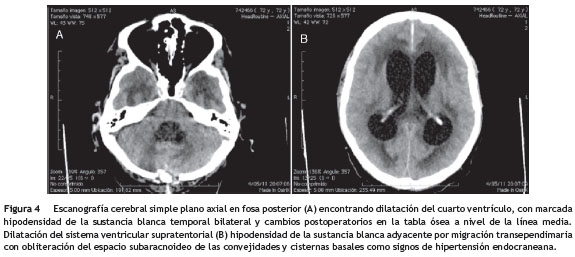

Al quinto día de biopsia de meninges, en escanografía cerebral simple de control, se observa hidrocefalia con importante migración transependimaria (fig. 4) por lo que se realiza ventriculostomía externa para derivación (fig. 5). En el postoperatorio, el paciente persiste con alteración del estado de conciencia por 3 semanas, con pobre respuesta verbal, motora y sin signos de respuesta inflamatoria sistémica; se realiza gastrostomía y traqueostomía. El paciente mejora lentamente el estado de conciencia, respuesta verbal y motora, se logra decanulación de traqueostomía y es dado de alta con trimetropin sulfa por un año. Un mes después del egreso fallece en casa por causa no determinada.

Se realizó punción lumbar de control al día 12 de tratamiento, con los hallazgos descritos en la tabla 1- B. Adenosina deaminasa (ADA) en 6,9 y ELISA para VIH, negativo. Permaneció hospitalizado por 37 días y dieron egreso. Tres días después presentó somnolencia, desorientación y alucinaciones visuales y consultó a nuestra institución. Al ingreso, somnoliento, desorientado y con lesiones subdérmicas en piel de consistencia blanda no adherida a planos profundos y dolorosas a la palpación, localizadas en extremidades. Se realizó escanografía cerebral simple que documenta leucomalacia en región cerebelosa derecha (fig. 1A), sin lesiones ni masas extraaxiales agudas (fig. 1B).